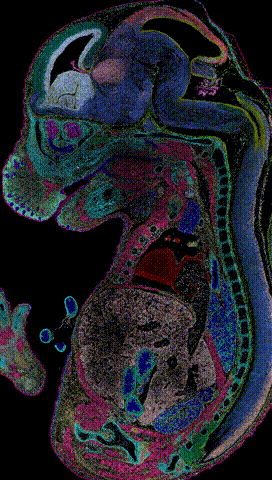

登上《细胞》杂志(Cell)封面的

小鼠胚胎发育时空图谱

基于这一技术

2022年5月

华大生命科学研究院绘制了

小鼠胚胎第9.5-16.5天时空图谱(受访者供图)

这个图谱

可以帮助人类更好地认识出生缺陷

华大免费公开了研究数据

与全世界科学家一起

探讨出生缺陷的解决办法